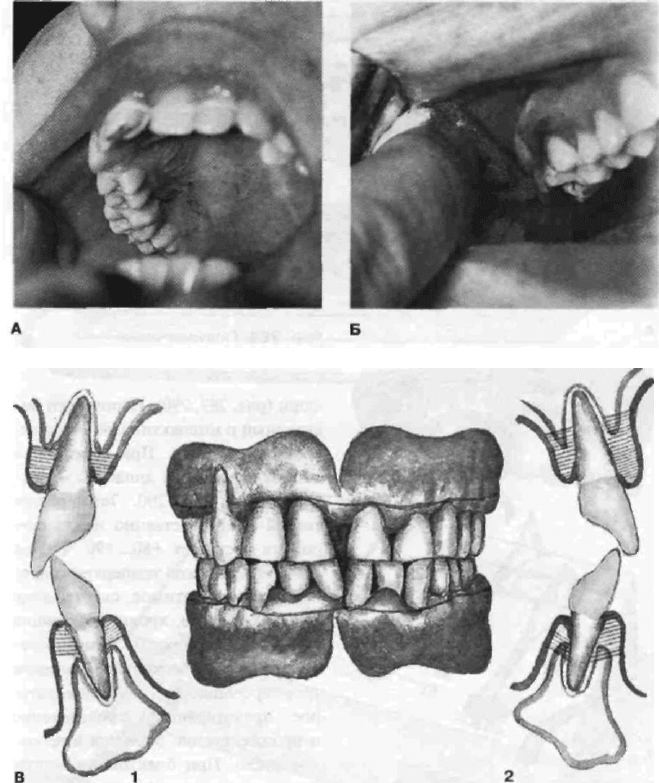

Рис. 290. Диатермокоагуляция паро-

донтальных карманов (схема):

А — электроды с различным положением

активных точек; Б — направление движения

электрода